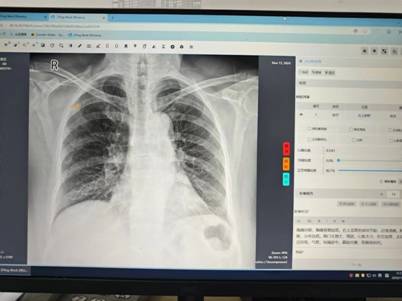

江苏省卫生健康云影像平台作为省级重点惠民医疗信息化工程,构建起全省医学影像数据共享体系,具备影像存储管理、跨区域调阅共享、检查结果互认及重复检查预警等功能,能够对胸部 x 光、ct 等影像进行智能分析。在肺结核早期诊断中,该平台的 ai 智能阅片系统通过抓取胸片关键信息并反馈诊断结果,一旦与原诊断存在差异,医院将立即组织专家复核,必要时安排进一步检查或转诊上级医院,有效减少漏诊误诊,提升基层结核病发现率。